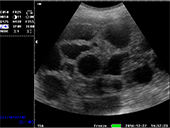

B模式 猪孕检

猪孕检

猪孕检

猪孕检